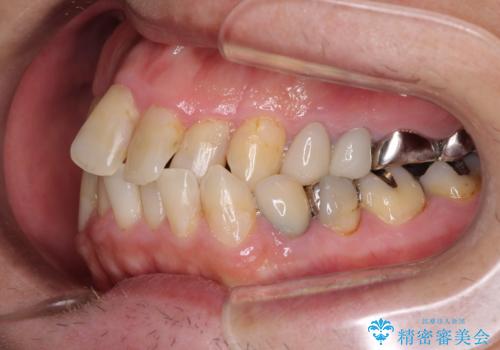

- 飛び出している上顎前歯と、奥歯に多くある銀歯を気にして来院された患者様です。

マウスピースで矯正を行いたい反面、一旦早めに前歯を整えたいというご希望があったため、まずは上顎前歯をワイヤー装置で整え、その後インビザラインにて仕上げていくこととしました。

矯正治療後には、奥歯の銀歯をすべてセラミックにて補綴治療することとしました。

ワイヤー矯正を併用したことで、上顎前歯はあっという間に整いました。

補綴治療にあたり、痛みのある歯に対して根管治療を行うこととしましたが、処置が必要な歯が多かったため、期間を要しました。

補綴治療中に前歯のデコボコが戻ってしまったため、補綴治療後にインビザラインを1セット追加して仕上げました。